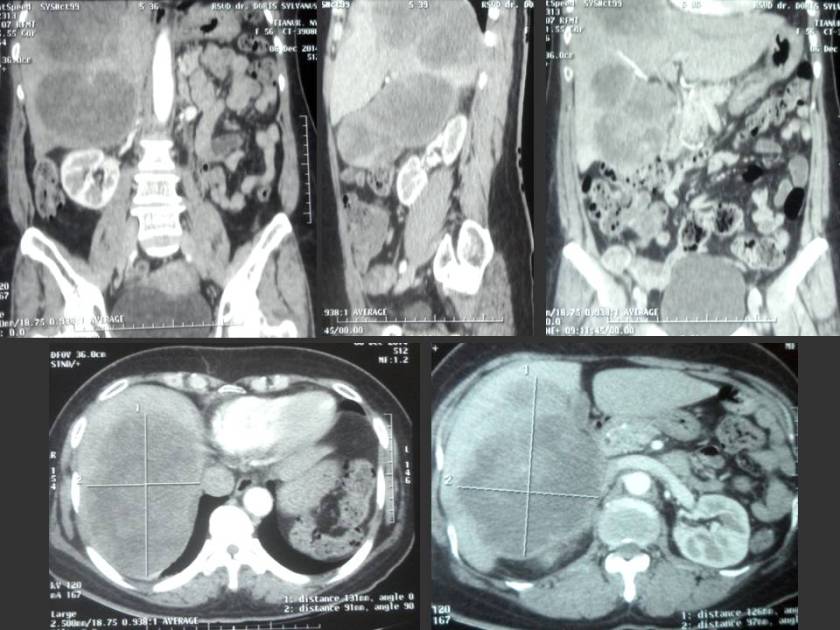

Alex (not real name) is 63 years old. His problem started about 3 years ago, in 2012 while visiting Australia he had severe pain in his right forearm. He was admitted into a hospital. An X-ray showed a growth in his lung. On returning home, Alex had a biopsy and was told that he had a high-grade undifferentiated soft tissue sarcoma in the right chest. The tumour was lodged behind the sternum but had spread onto the first rib. It was stage 3 cancer.

Alex underwent chemotherapy in December 2012. The regime used was Doxorubicin and Ifosfamide. The tumor shrank a bit. Then Alex had a surgery. This operation was done in a heart hospital in early 2013. During this surgery the doctor also did a by-pass for his heart. (Note: Alex underwent an angioplasty in the same hospital in 2004).

After the surgery, Alex had 36 sessions of radiotherapy.

A small tumor on the first rib was not removed during the surgery and this started to grow again. Alex underwent another surgery in June 2014. This time the surgery to remove the first rib and part of second rib was done in Singapore. After the surgery, Alex received another 36 sessions of radiation in October 2014 in a Malaysian hospital.

Hardly 2 months later, the tumor spread to the right lung membrane, spewing fluid into three-fourth of his right lung. Alex had to be hospitalised and fluid was tapped out. This happened in late in November 2014.

A CT scan in mid-March 2015, showed no improvement and the drug treatment was stopped on 26 March 2015.